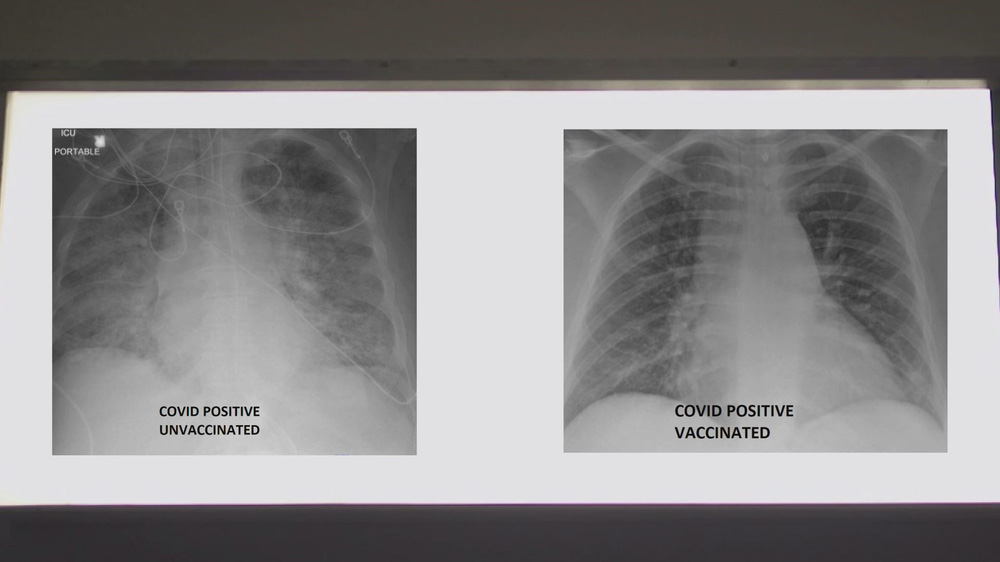

Để xem vaccine COVID-19 có thể giúp ích như thế nào, Bệnh viện SSM Health đã cung cấp hai bức ảnh chụp X-quang phổi của 2 bệnh nhân COVID-19 cho đài KSDK. Trong hai người này, một người đã được tiêm vaccine COVID-19, một chưa chưa tiêm.

Tiến sĩ Kamel đã xem phim chụp X-quang và giải thích chất màu trắng trong phổi mà bạn nhìn thấy chính là tác động của virus. Đó có thể là vi khuẩn, chất nhầy hoặc dịch tiết, tiến sĩ nói.

Tuy nhiên, tiến sĩ Kamel đã phân tích về sự khác biệt có thể thấy trên phim chụp X-quang.

Ông cho biết khi nhìn vào hình chụp X-quang của người chưa được tiêm vaccine COVID-19, ông đánh giá đây rất có thể một bệnh nhân cần được hỗ trợ.

"Họ chắc chắn ít nhất cũng cần oxy và đôi khi họ cần nhiều hơn thế. Họ có thể cần dùng máy thở hoặc được đặt nội khí quản, dùng thuốc an thần và về cơ bản là hỗ trợ sự sống", tiến sĩ Kamel nói.

Còn nếu bạn nhìn vào hình ảnh của người đã tiêm vaccine, bạn sẽ thấy nhiều màu đen hơn. Tiến sĩ Kamel giải thích: Khi phổi chứa đầy không khí, nó sẽ có màu đen trong phim X-quang. Như vậy, bức ảnh này có nhiều màu đen hơn ảnh trước.

Chủ nhân của phim X-quang này mắc COVID-19 dù đã được tiêm vaccine - một trường hợp hiếm khi xảy ra. Chỉ dưới 1% những người được tiêm vaccine bị nhiễm COVID-19.

So sánh ảnh chụp phổi của bệnh nhân COVID-19 không tiêm và có tiêm vaccine. Ảnh: KSDK